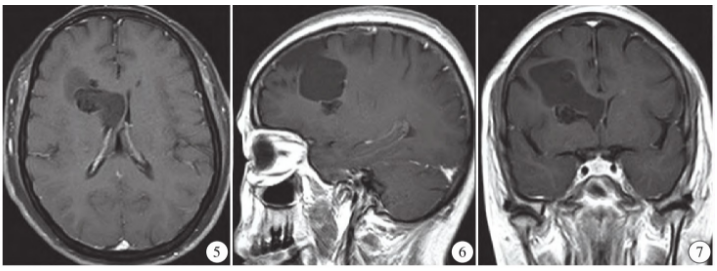

MRI平扫显示右侧额叶不规则团块状混杂信号影,大小约4.3 cm×3.7 cm×4.0 cm,呈T1WI低T2WI稍高及FLAIR稍高信号为主,其间见结节状T1WI低T2WI低FLAIR低信号,病灶向内凸向脑组织,深达右侧脑室旁(图2~4);增强扫描病灶中心无强化,部分壁轻度强化(图5~7);考虑右侧额叶囊性肿瘤性病变并钙化。

图5~7 T1WI+C/SAG/COR/TRAXIA显示中心无强化,部分壁轻度强化。